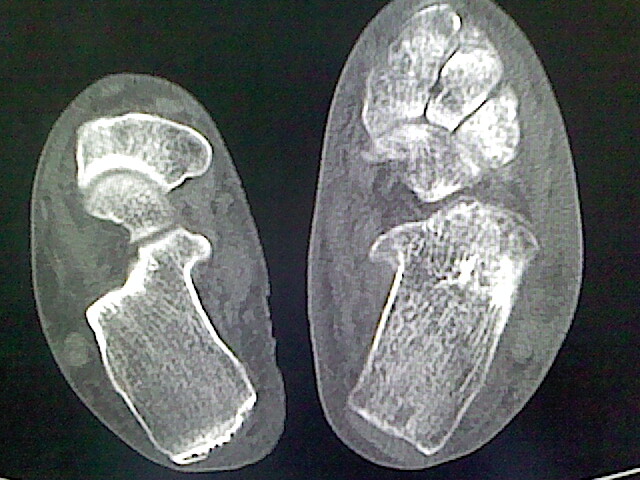

标题: CT16814:男,76岁,左小腿疼痛,不能站立 大家给看看 [打印本页]

男,76岁,左小腿疼痛,不能站立

本例骨质改变主要表现为滑膜或韧带区的骨侵蚀融解(胫腓联合区骨质破坏无硬化边),距骨后部骨质破坏区有硬化边及死骨样改变.所以,本例考虑关节结核可能性大,绒毛膜结节性滑膜炎多发于中年,且极少见于膝髋以外的关节,骨质硬坏也以压陷吸收为主,有明显的硬化边,骨膜增生呈结节状(可以mr鉴别),所以本例暂除外.

另不除外可引起相似表现的其他炎症如布氏杆菌性关节炎等